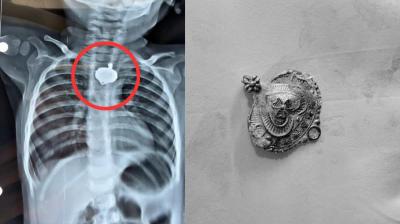

बड़वानी में 9 माह के बच्चे की आहार नली में फंसा मंगलसूत्र, डेढ़ महीने बाद एक्स-रे से खुलासा

24 Nov, 2025 08:30 AM IST | NARADMUNILIVE.COM

बड़वानी: रविवार को जिला अस्पताल में एक बेहद संवेदनशील और हैरान करने वाला मामला सामने आया. जब 9 माह के एक बच्चे के गले में मंगलसूत्र फंसा हुआ देखा गया. घटना...